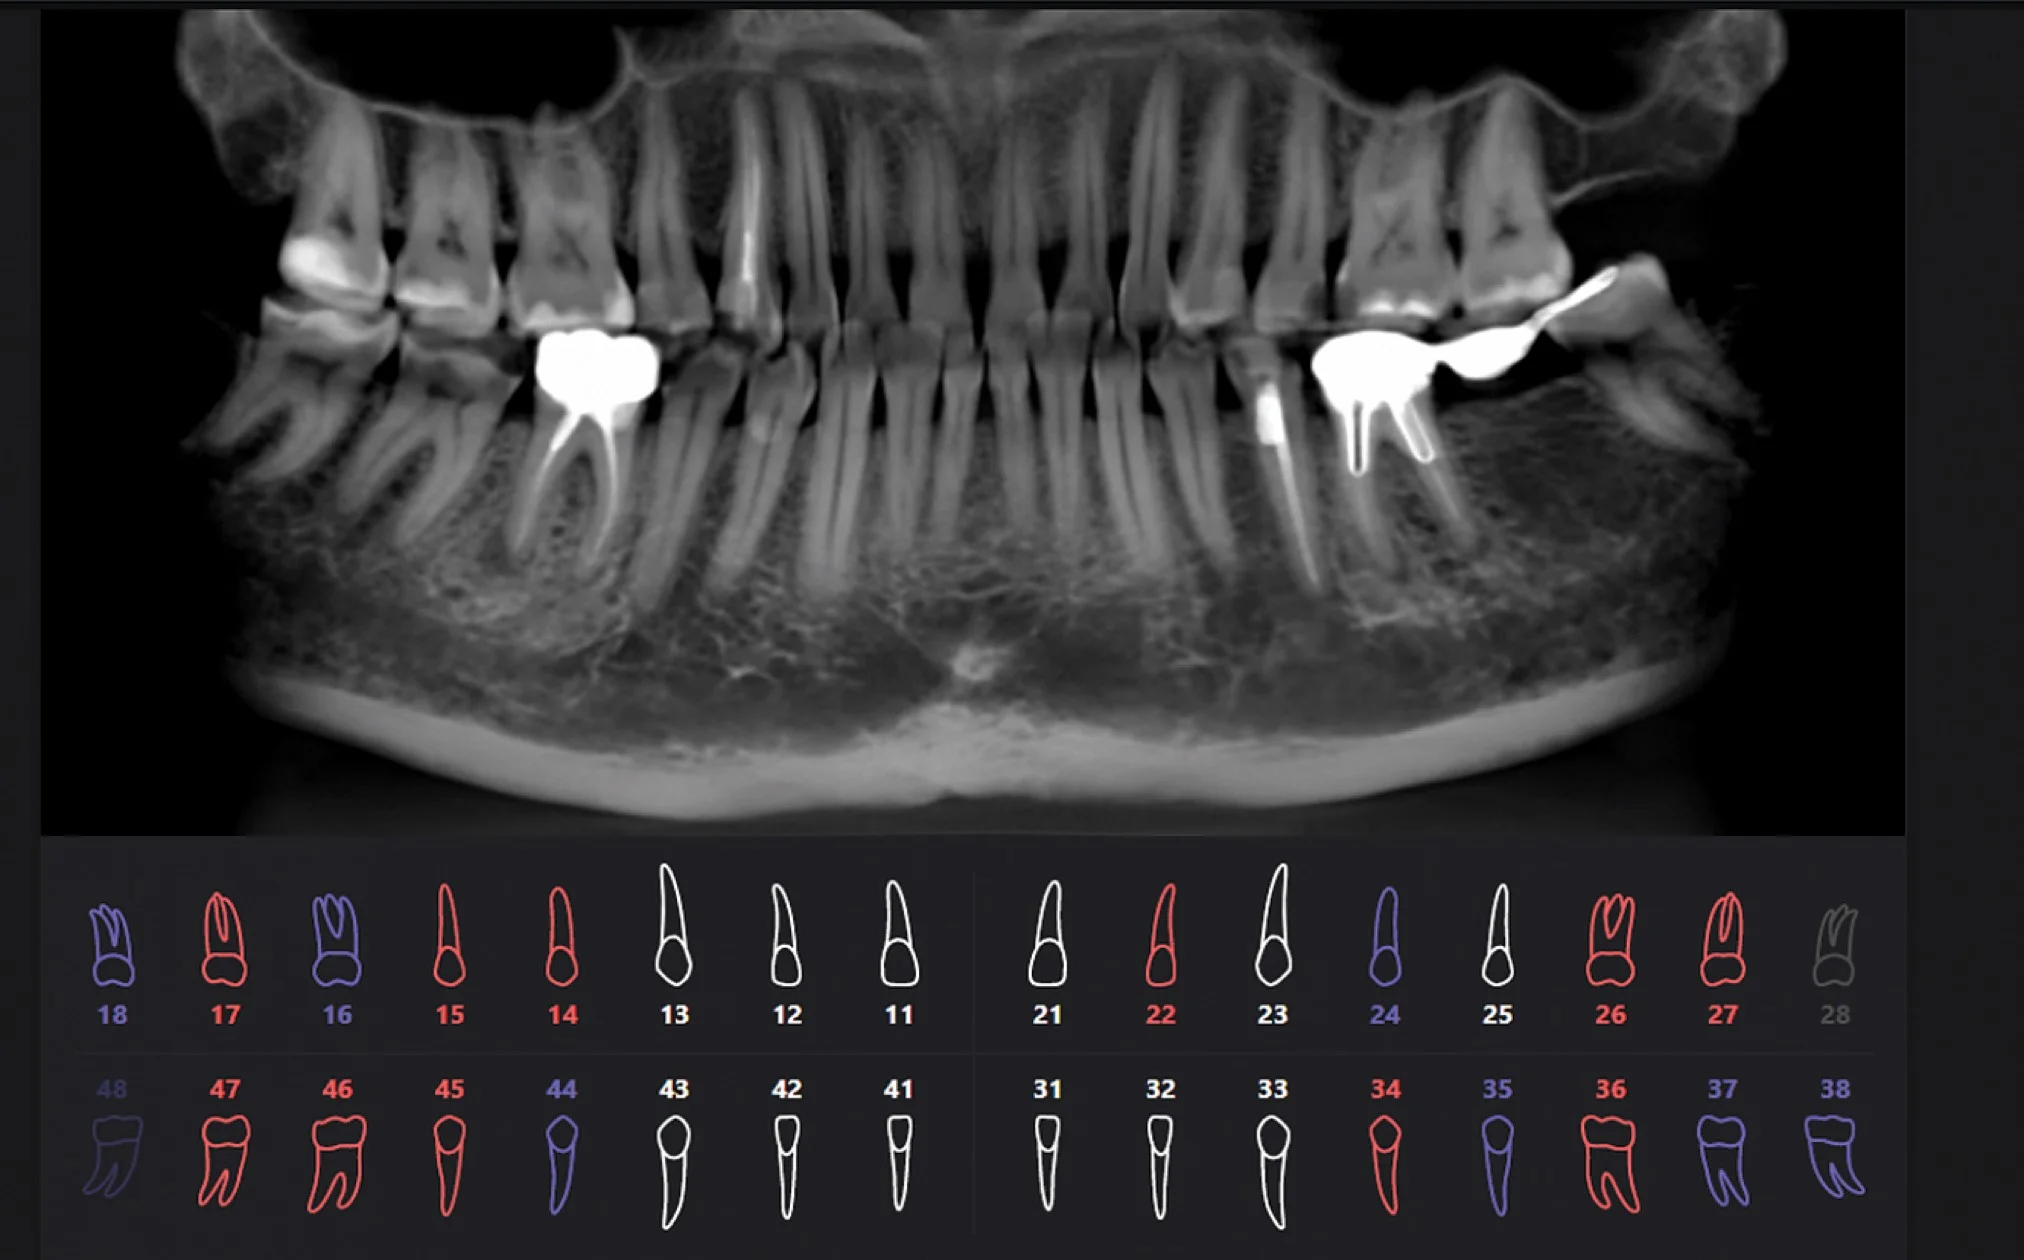

Результат работы искусственного интеллекта

Красным цветом показаны проблемные зубы, синим цветом — зубы с пломбами или ортопедическими конструкциями, белым цветом — здоровые зубы.

Когда мнение врача и искусственного интеллекта отличается

Мнение врача и искусственного интеллекта иногда может отличаться, это сигнал для того, чтобы более глубокого изучить проблемную область, назначить ремтерапию, динамическое наблюдение.

Определяющее мнение всегда остается за врачом.